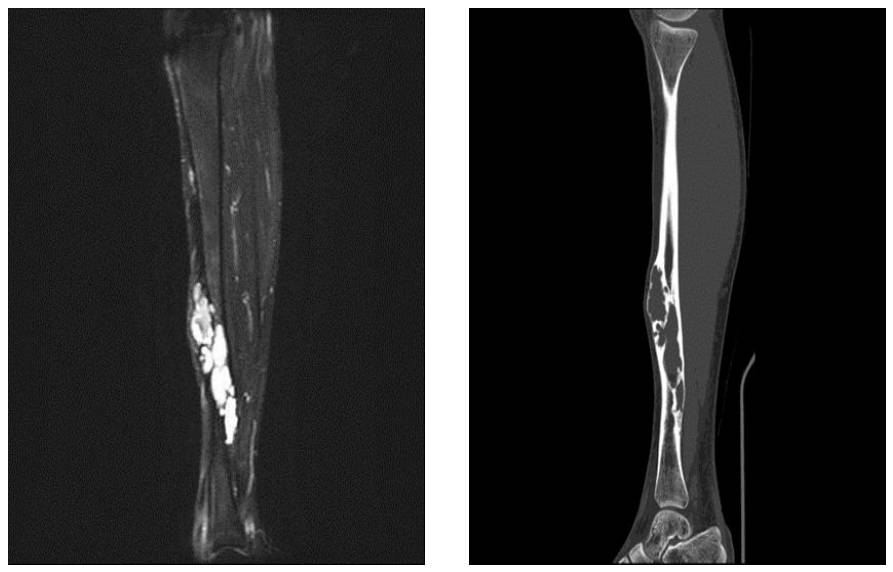

Ameliyat Öncesi: MR’da kistik içerik tomografide ise harabiyet daha ayrıntılı görülmekte